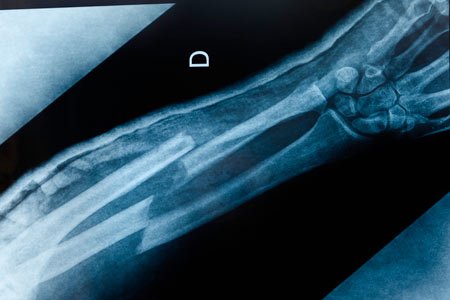

Broken bones, fractures and dislocations are common injuries. But they also demand quick, expert care in order to heal correctly. The members of the broken bones and trauma team at Henry Ford Health are leaders in the field. We provide expert care for even the most complex broken bones and orthopedic trauma.

Henry Ford Hospital, our Level I trauma center, features a dedicated orthopedic trauma operating room for complex injuries. Our multispecialty team of musculoskeletal traumatologists, trauma-trained physician assistants and nurse practitioners works together to quickly treat even the most serious traumas.